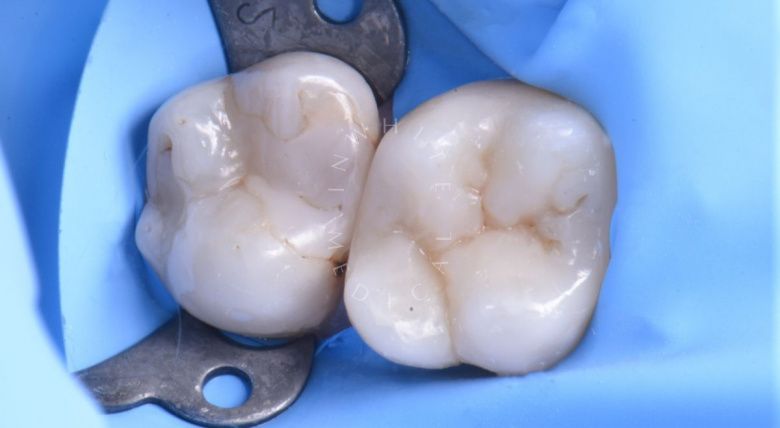

Художественная реставрация формы зубов

Стоматология Москва лучшие клиники. Художественная реставрация формы зубов - до процедуры